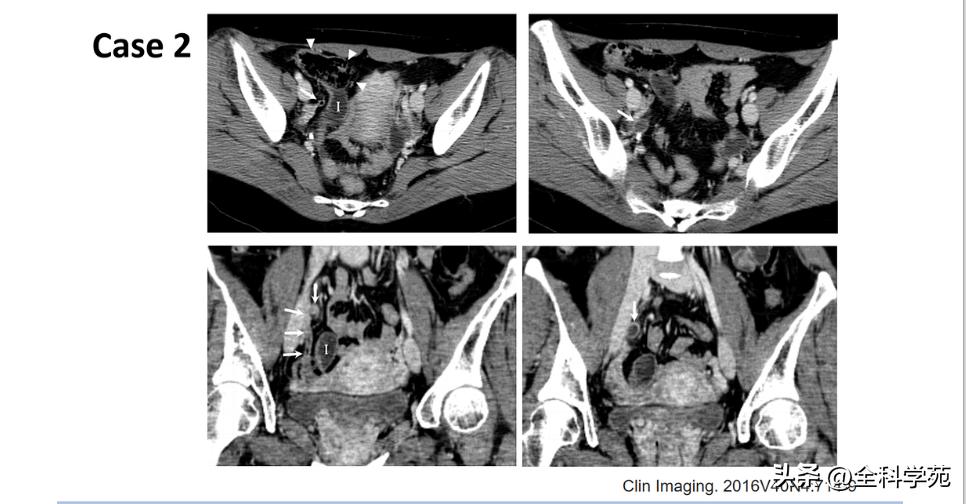

◆ 穿孔 (Perforation)

◆ 局部低强化是穿孔征象

◆ 蜂窝织炎和脓肿 (Phlegmon and abscess

◆ 门静脉炎 (Pylephlebitis)